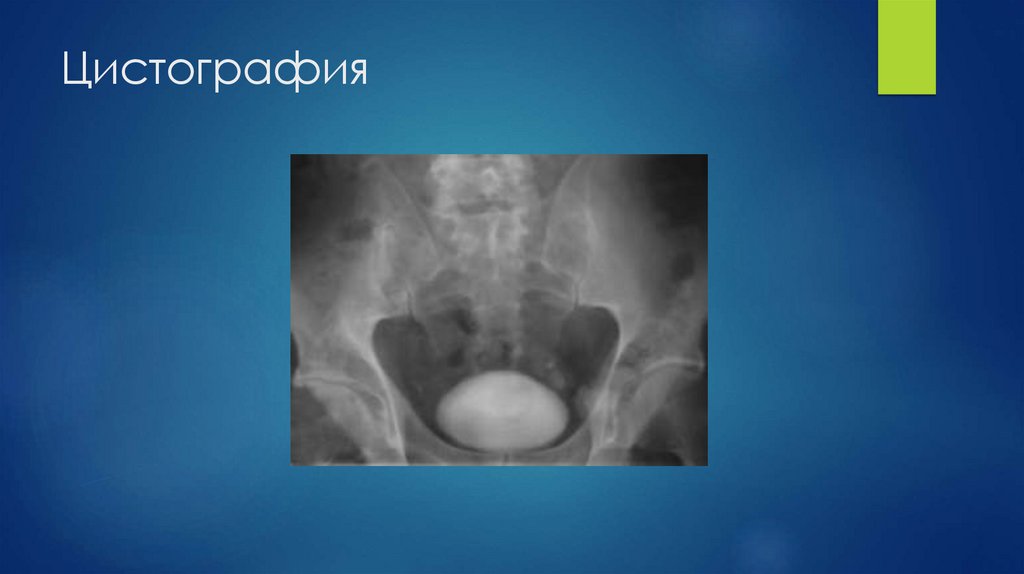

52. Цистография

53.

Дивертикул мочевого пузыря

ПМР

54.

Дефект наполнения МП

Разрыв мочевого пузыря